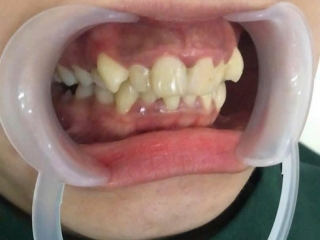

Cắt lợi làm dài thân răng và mài xương ổ cho KH Combodia – Giải pháp cho nụ cười cân đối, khỏe đẹp

Đó cũng là lý do mà khách hàng từ Cambodia đã không ngần ngại vượt hàng trăm km sang Việt Nam, tìm đến Nha Khoa Ân Đức Luxury để được bác sĩ Tài trực tiếp thăm khám và thực hiện cắt lợi làm dài thân răng kết hợp mài xương ổ.